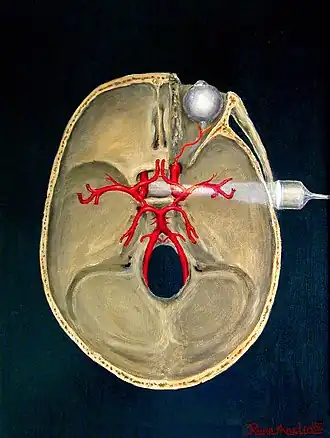

There are no standards for displaying color Doppler. Some laboratories show arteries as red and veins as blue, as medical illustrators usually show them, even though some vessels may have portions flowing toward and portions flowing away from the transducer. This results in the illogical appearance of a vessel being partly a vein and partly an artery. Other laboratories use red to indicate flow toward the transducer and blue away from the transducer. Still other laboratories display the Doppler color map in accordance with published data, with red shift representing longer wavelengths (scattered) from blood flowing away from the transducer and blue representing the shorter wavelengths from blood flowing toward the transducer. Because of this confusion and lack of standards, the sonographer must understand the underlying physics of color Doppler and the physiology of normal and abnormal blood flow in the human body (see Red shift).[4][5][6]